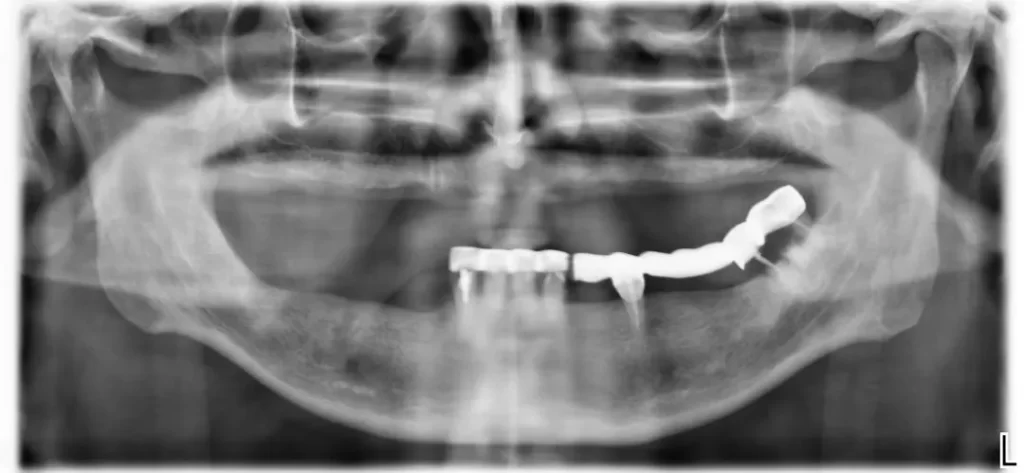

За Вас през последните две години д-р Маринов Jr. разработи и доусъвършенства дигиталната методика за приложение на Хирургичните водачи в съответствие с метода на Malo – All on 4.

Това е гаранцията за изключително точно позициониране на дисталните – задни зъбни импланти спрямо максиларните синуси в горната челюст и долночелюстния канал на n. mandibularis в долната челюст по време на хирургичната операция.

По отношение на хирургията е важно, че зъбните импланти на Nobel не са режещи, а са разпъващи. При тънка кост това дава възможност, самите импланти да се използват като експандери по отношение на кортикалните стени на наличната тънка кост.